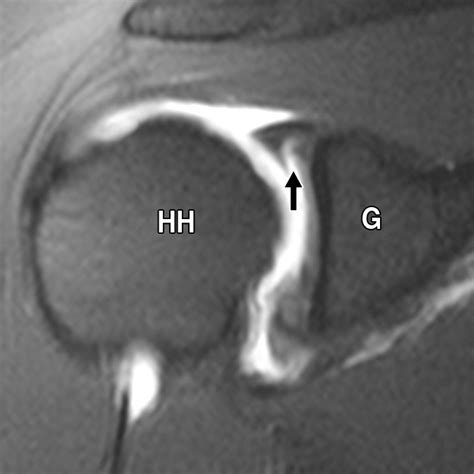

Diagnosing a labrum detachment shoulder involves a combination of medical history, physical examination, and imaging tests. The diagnostic process typically includes:

• Imaging Tests: Imaging studies such as X-rays, MRI, or CT scans can provide detailed images of the shoulder joint and help identify the location and extent of the labrum detachment.